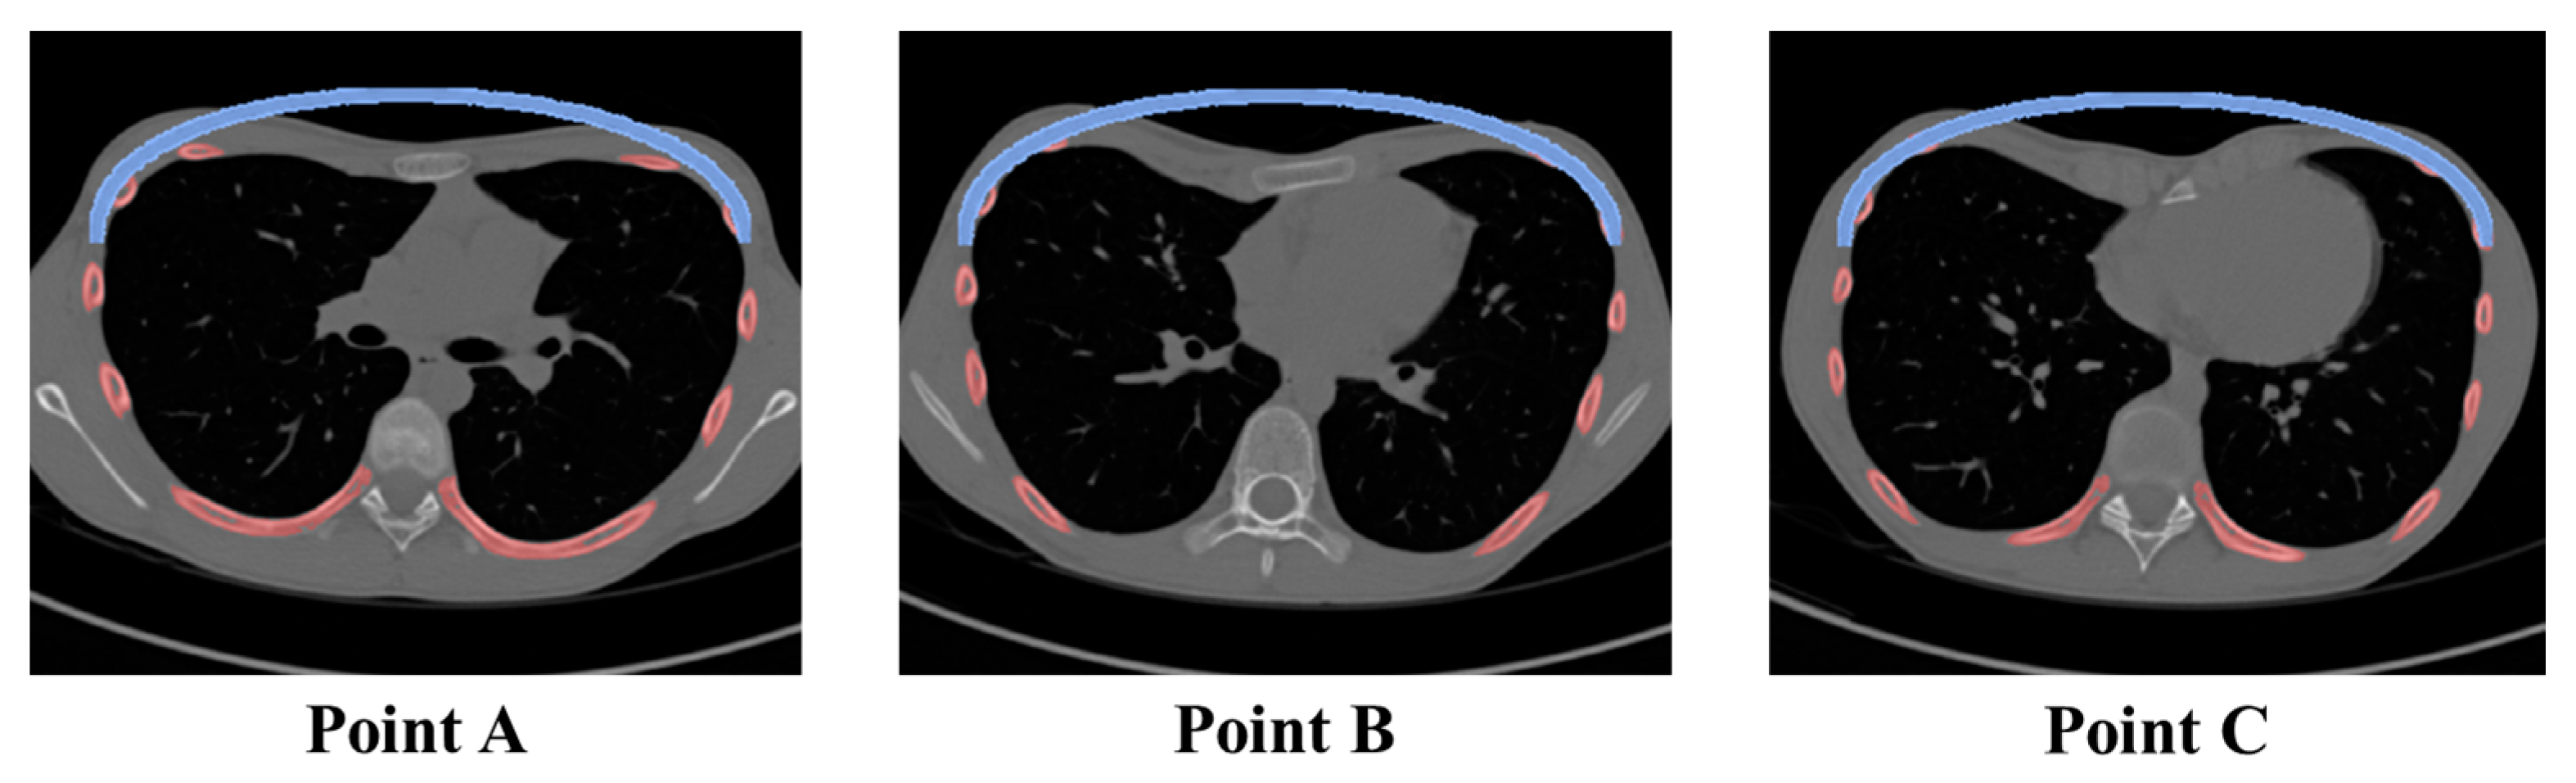

| Point | A (mm): Pre-Op. | A’ (mm): Post-Op. | B (mm): Pre-Op. | C (mm): Post-Op. | HI: Pre-Op. | ICI: Post-Op. |

|---|---|---|---|---|---|---|

| A | 217.86 | 206.97 | 73.01 | 101.11 | 2.98 | 2.05 |

| B | 215.22 | 204.46 | 68.61 | 103.49 | 3.14 | 1.98 |

| C | 217.57 | 206.70 | 73.30 | 104.15 | 2.97 | 1.98 |